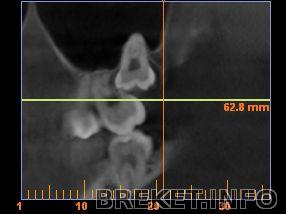

А это верхняя, сейчас она ещё больше в 7ке...

). А верхняя 8ка уже вросла в 7ку так, что её удаление возможно только через удаление 7ки, и если меня пока не беспокоят болями и кариесом эти зубы - смысла в этом нет.

Орт: ...к тому же, после того как мы наклоним 7ку правильно (она благодаря 8ке растет в щеку под углом около 45градусов), возможно, станет получше.

ИринаМ да если бы это было так просто - я бы тоже удалила (что и сделала с единственной выросшей, списав её якобы из-за кариеса, а по факту - нах мне зуб, растущий в щёку, не участвующий в жевании и чувствительный при чистке?) Но как вот удалить вторую верхнюю? Удалив ради нее и 7ку? Так вообще без зубов остаться можно, и так нет 4ок и 5ки... Хирург ведь заставил снимок делать, даже 6-месячной давности не принял, по свеженькому посмотрел и показал линейкой путь выхода зуба при удалении, и что четверть зуба в семерке (в корнях, частично их рассосав), и удалить можно только через нее. Ну верхняя ещё ладно, она нашла себе положение и, можно сказать, "выросла", просто неправильно, он обещал что дальше она не поползет, корни сформированы, коронка частично вылезла из десны. Про то что она в гайморовой пазухе корнями вообще молчу...